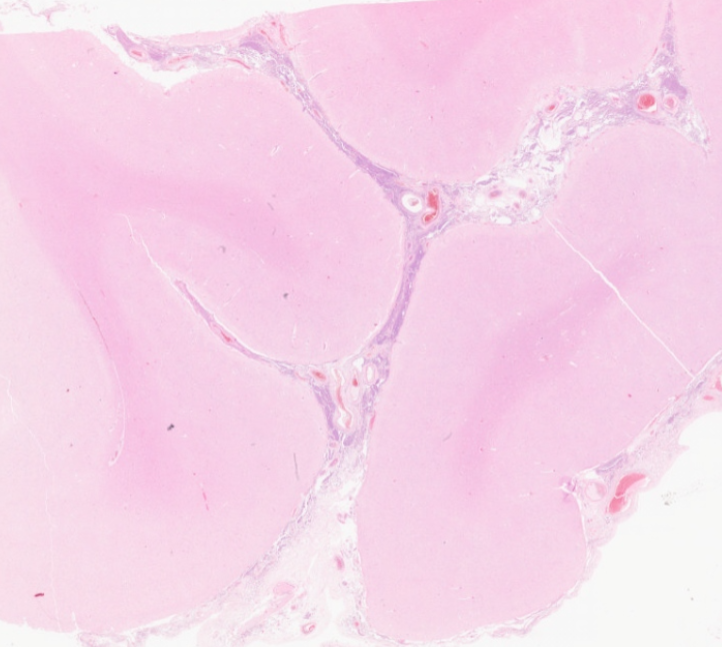

What neoplasm is causing this clavicular mass in a 65 year old man? View the whole slide on the Leeds Virtual Pathology Website here 🔬🔬🔬virtualpathology.leeds.ac.uk/slides/library… #softtissuepath #pathX #caseoftheweek